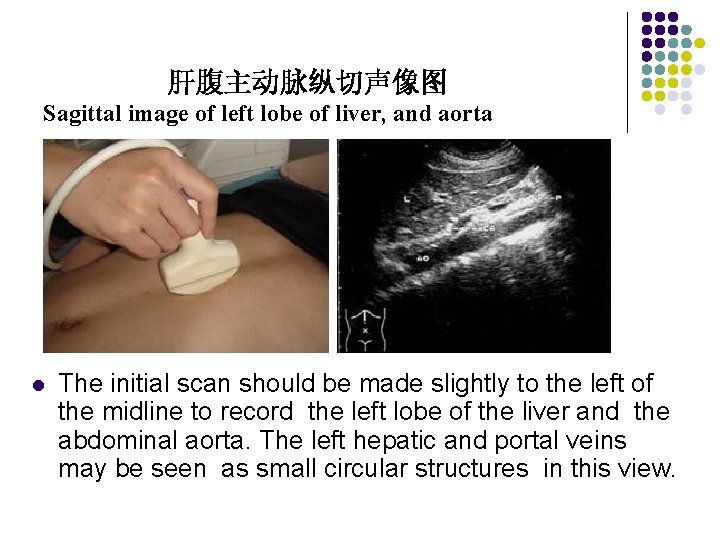

Longitudinal Scan Plane l Scan Ⅰ The initial scan should be made slightly to the left of the midline to record the left lobe of the liver and the abdominal aorta. The left hepatic and portal veins may be seen as small circular structures in this view.

肝腹主动脉纵切声像图 Sagittal image of left lobe of liver, and aorta l The initial scan should be made slightly to the left of the midline to record the left lobe of the liver and the abdominal aorta. The left hepatic and portal veins may be seen as small circular structures in this view.